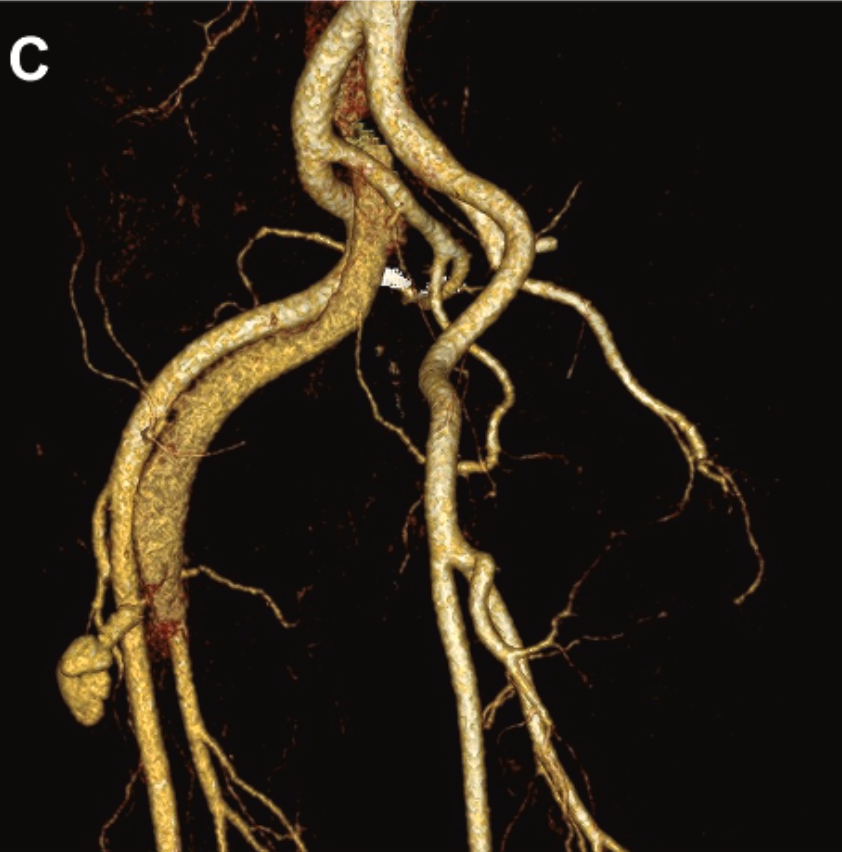

Better visualization, smarter planning. In this JVS-VL pilot study, CEUS + UHFUS showed promise for improving preop mapping and streamlining LVA in patients with lymphedema.